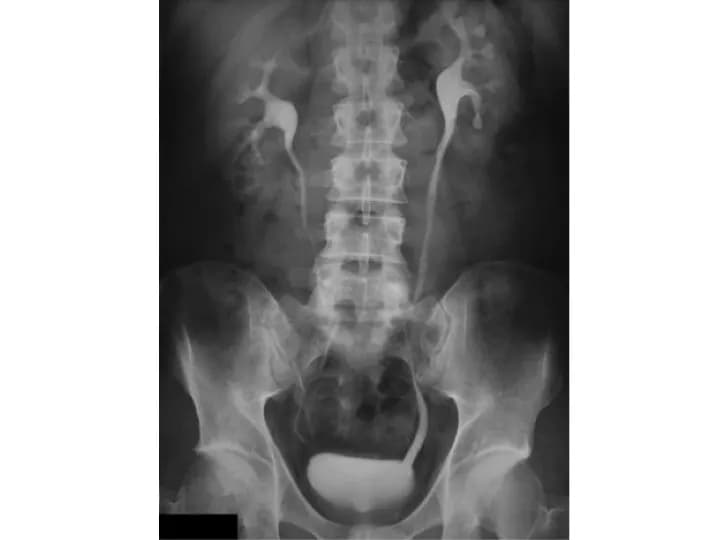

Intravenous Pyelogram

• Intravenous Pyelogram (IVP) is an X-ray examination of the kidney, ureter, and bladder

• The contrast material collects in the kidney and urinary tract and is displayed on X-ray images, which could be used to interpret the anatomy and function of these organs

The IVP procedure involves X-ray exposure to the lower abdominal and groin region.

• The Intravenous Pyelogram procedure helps to evaluate the anatomy and function of kidney, urinary tract, and urinary bladder

• It helps in detecting various health conditions, such as kidney stones, surgery on urinary tract, enlarged prostate, blood in the urine, congenital anomalies of the urinary tract, and tumors in the kidney or urinary tract